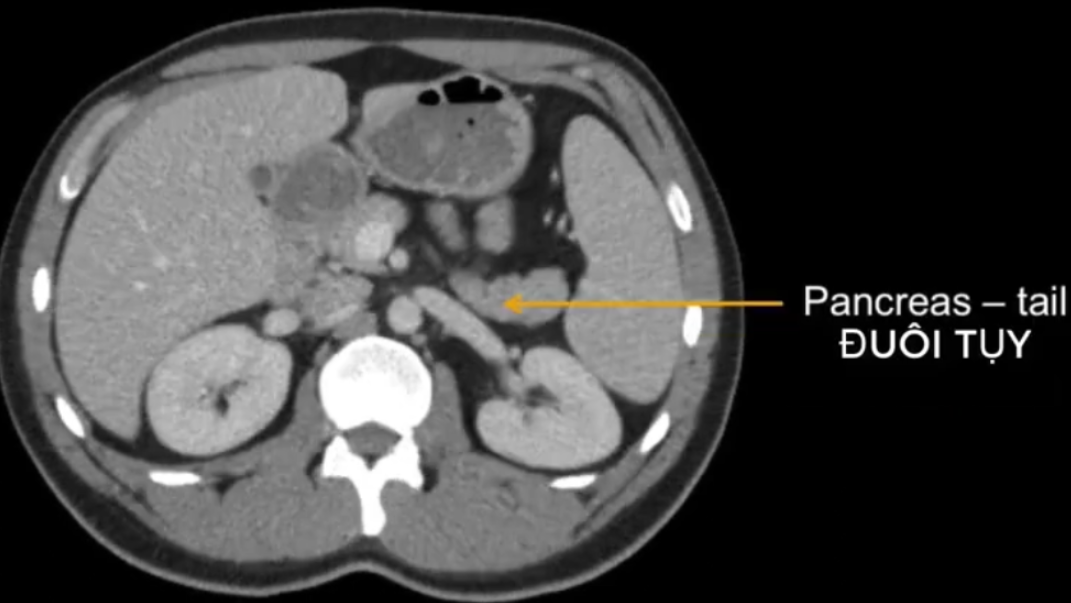

cq trong hình ?